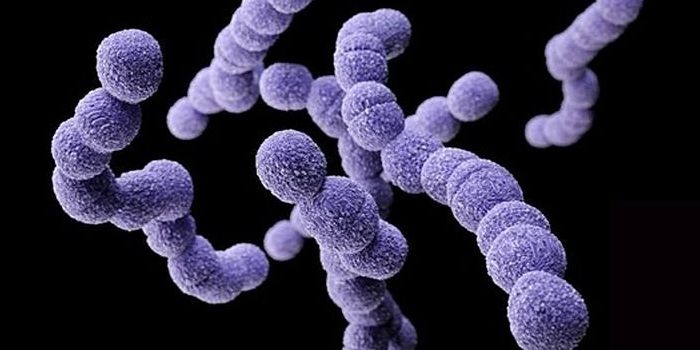

JAN 31, 2016MicrobiologyResearchers at the University of Notre Dame identified the mechanism by which Streptococcus pyogenes, also known as Grou ...